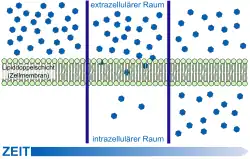

Die einfachste Form des Transportes durch die Blut-Hirn-Schranke stellt die freie Diffusion dar. Dieser auch als passiver Transport bezeichnete Austausch kann prinzipiell sowohl durch die Zellmembran der Endothelien als auch durch die Tight Junctions stattfinden. Dabei wird – wie bei jeder Diffusion – ein Konzentrationsausgleich oder der Ausgleich eines elektrochemischen Gradienten angestrebt. Bei der freien Diffusion wird für den Membrantransport keine Energie aus der Zelle benötigt. Der Materialfluss ist proportional zur Konzentration und kann von der Zelle nicht reguliert werden.[101]

Die lipophilen („fettfreundlichen“) Eigenschaften der Zellmembran und ihre dichte Verknüpfung über die Tight Junctions reduzieren die Zahl der Substanzen, die durch Diffusion die Blut-Hirn-Schranke überwinden können, allerdings erheblich. Die Durchlässigkeit der Blut-Hirn-Schranke für ein bestimmtes Molekül steht in direktem Verhältnis zu seiner Lipophilie.[102] Bezüglich der molaren Masse verhält es sich umgekehrt proportional. Das heißt, je lipophiler und kleiner eine Verbindung ist, umso leichter kann sie durch das Endothel hindurch diffundieren.[11] Für die molare Masse eines Moleküls wird als Grenzwert eine maximale Größe von 400 bis 500 g·mol−1 bei einer intakten Blut-Hirn-Schranke angegeben. Moleküle oberhalb dieses Grenzwertes können nicht durch die Blut-Hirn-Schranke diffundieren. Man darf die Blut-Hirn-Schranke allerdings nicht als diskrete Barriere verstehen, die eine bestimmte Molekülgröße komplett zurückhält und einer kleineren vollständig die Diffusion in das Gehirn ermöglicht. Die Diffusionsprozesse an der Blut-Hirn-Schranke sind dynamische Gleichgewichte. Für ein Molekül mit einer Querschnittsfläche von 0,52 nm², was einer molaren Masse von etwa 200 g·mol−1 entspricht, ist die Blut-Hirn-Schranke um den Faktor 100 durchlässiger als für ein Molekül mit einer Fläche von 1,05 nm² (= 450 g·mol−1).[20][103]

Der Göttinger Biophysiker Hermann Träuble entwickelte 1971 eine Theorie über den Transport von kleinen Molekülen durch die Zellmembran. Danach sind kleine, zwischen den Fettsäureketten der Lipiddoppelschichten befindliche Hohlräume für den diffusen Transport verantwortlich. Die Hohlräume entstehen durch Übergänge der anti- zur gauche-Konformation (trans-gauche-trans Kinks) in den Fettsäureresten der Phospholipide der Zellmembran. Zwischen diesen Konformationsübergängen liegen nur sehr niedrige Energieschwellen. Die Kinks (engl. kink ‚Knick‘) sind beweglich und wandern mit dem zu transportierenden Molekül durch die Membran.[104][105][106][107] Träubles Theorie wurde 1974 von Anna und Joachim Seelig NMR-spektroskopisch bestätigt.[108][109]

Bezüglich der Lipophilie ist der Verteilungskoeffizient in Oktanol/Wasser ein wichtiger Indikator für die Fähigkeit einer Substanz, durch die Blut-Hirn-Schranke diffundieren zu können.[110] Der Verteilungskoeffizient wird üblicherweise in logarithmischer Form als log P angegeben. Ein log P-Wert einer Substanz von beispielsweise 3,8 bedeutet dabei, dass diese Substanz sich in einer um den Faktor 103,8 höheren Konzentration in Oktanol (lipophil) als in Wasser (hydrophil) verteilt. Liegt der log P-Wert bei 0, so verteilt sich die Substanz in beiden Phasen gleich, ist er negativ, so ist die Substanz hydrophil. Lipophile Substanzen können prinzipiell am leichtesten die aus Fettsäuren aufgebaute Plasmamembran der Zellen passieren. Liegt der log P-Wert oberhalb von 3, so nimmt dieser Effekt meist wieder ab, da solche Moleküle eine hohe Bindungsaffinität zu Plasmaproteinen haben.